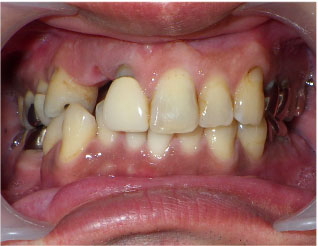

この方は歯並びもかなり悪く、虫歯も重度でした。

抜歯する歯もありましたがブリッジで治す事が出来ました。

1回目の治療時に仮歯を入れますのですぐに歯が入りますし、虫歯で欠けたりしている部分も無くなります。

当院のセラミック法でしたら歯並びも重度虫歯も一緒に治療が可能です。